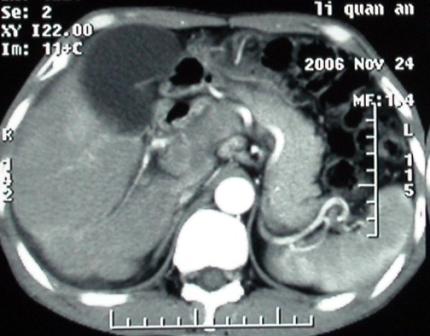

补充一点重要资料:今日查afp大于正常值10倍以上。因此,本病例最大可能应该是肝癌。

手术结果:

肝脏尾状叶肝癌(沿肝十二指肠韧带向下韧带内生长,门腔间隙外压增大),大结节性肝硬化,胆囊积脓,胆道感染。术中见肝外胆道2cm直径,肿瘤向前压迫胆管至扁平状态。